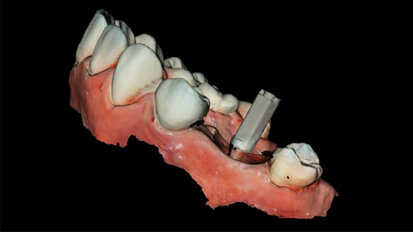

Rekonstrukce chrupu v dolní čelisti

Rekonstrukce v dolní čelisti popsaná v následující kazuistice byla provedena pomocí ASTRA TECH Implant System® EV a konceptu SmartFix® (Dentsply ...